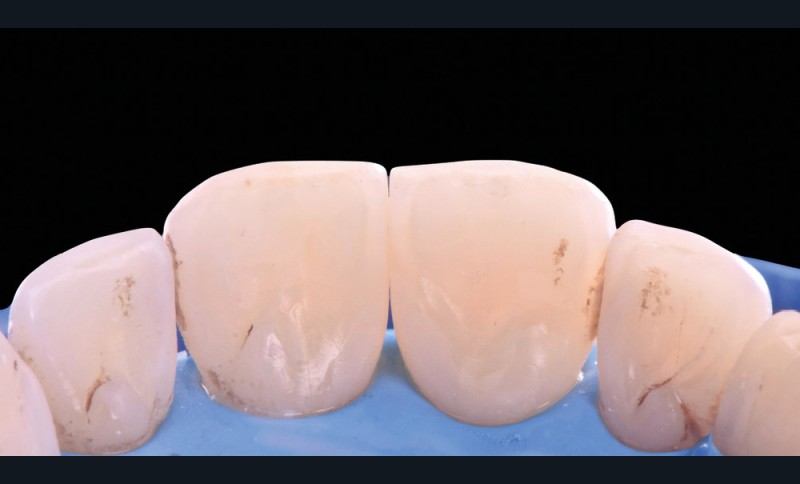

Les triangles noirs

Ils correspondent à une perte de papille interdentaire et sont principalement observés :

– lorsque la distance point de contact/crête osseuse est supérieure à 5 mm ;

– chez des patients présentant une atteinte parodontale avec une perte osseuse associée à une récession horizontale ;

– pour des dents le plus souvent de forme triangulaires ;

– en post-traitement orthodontique.